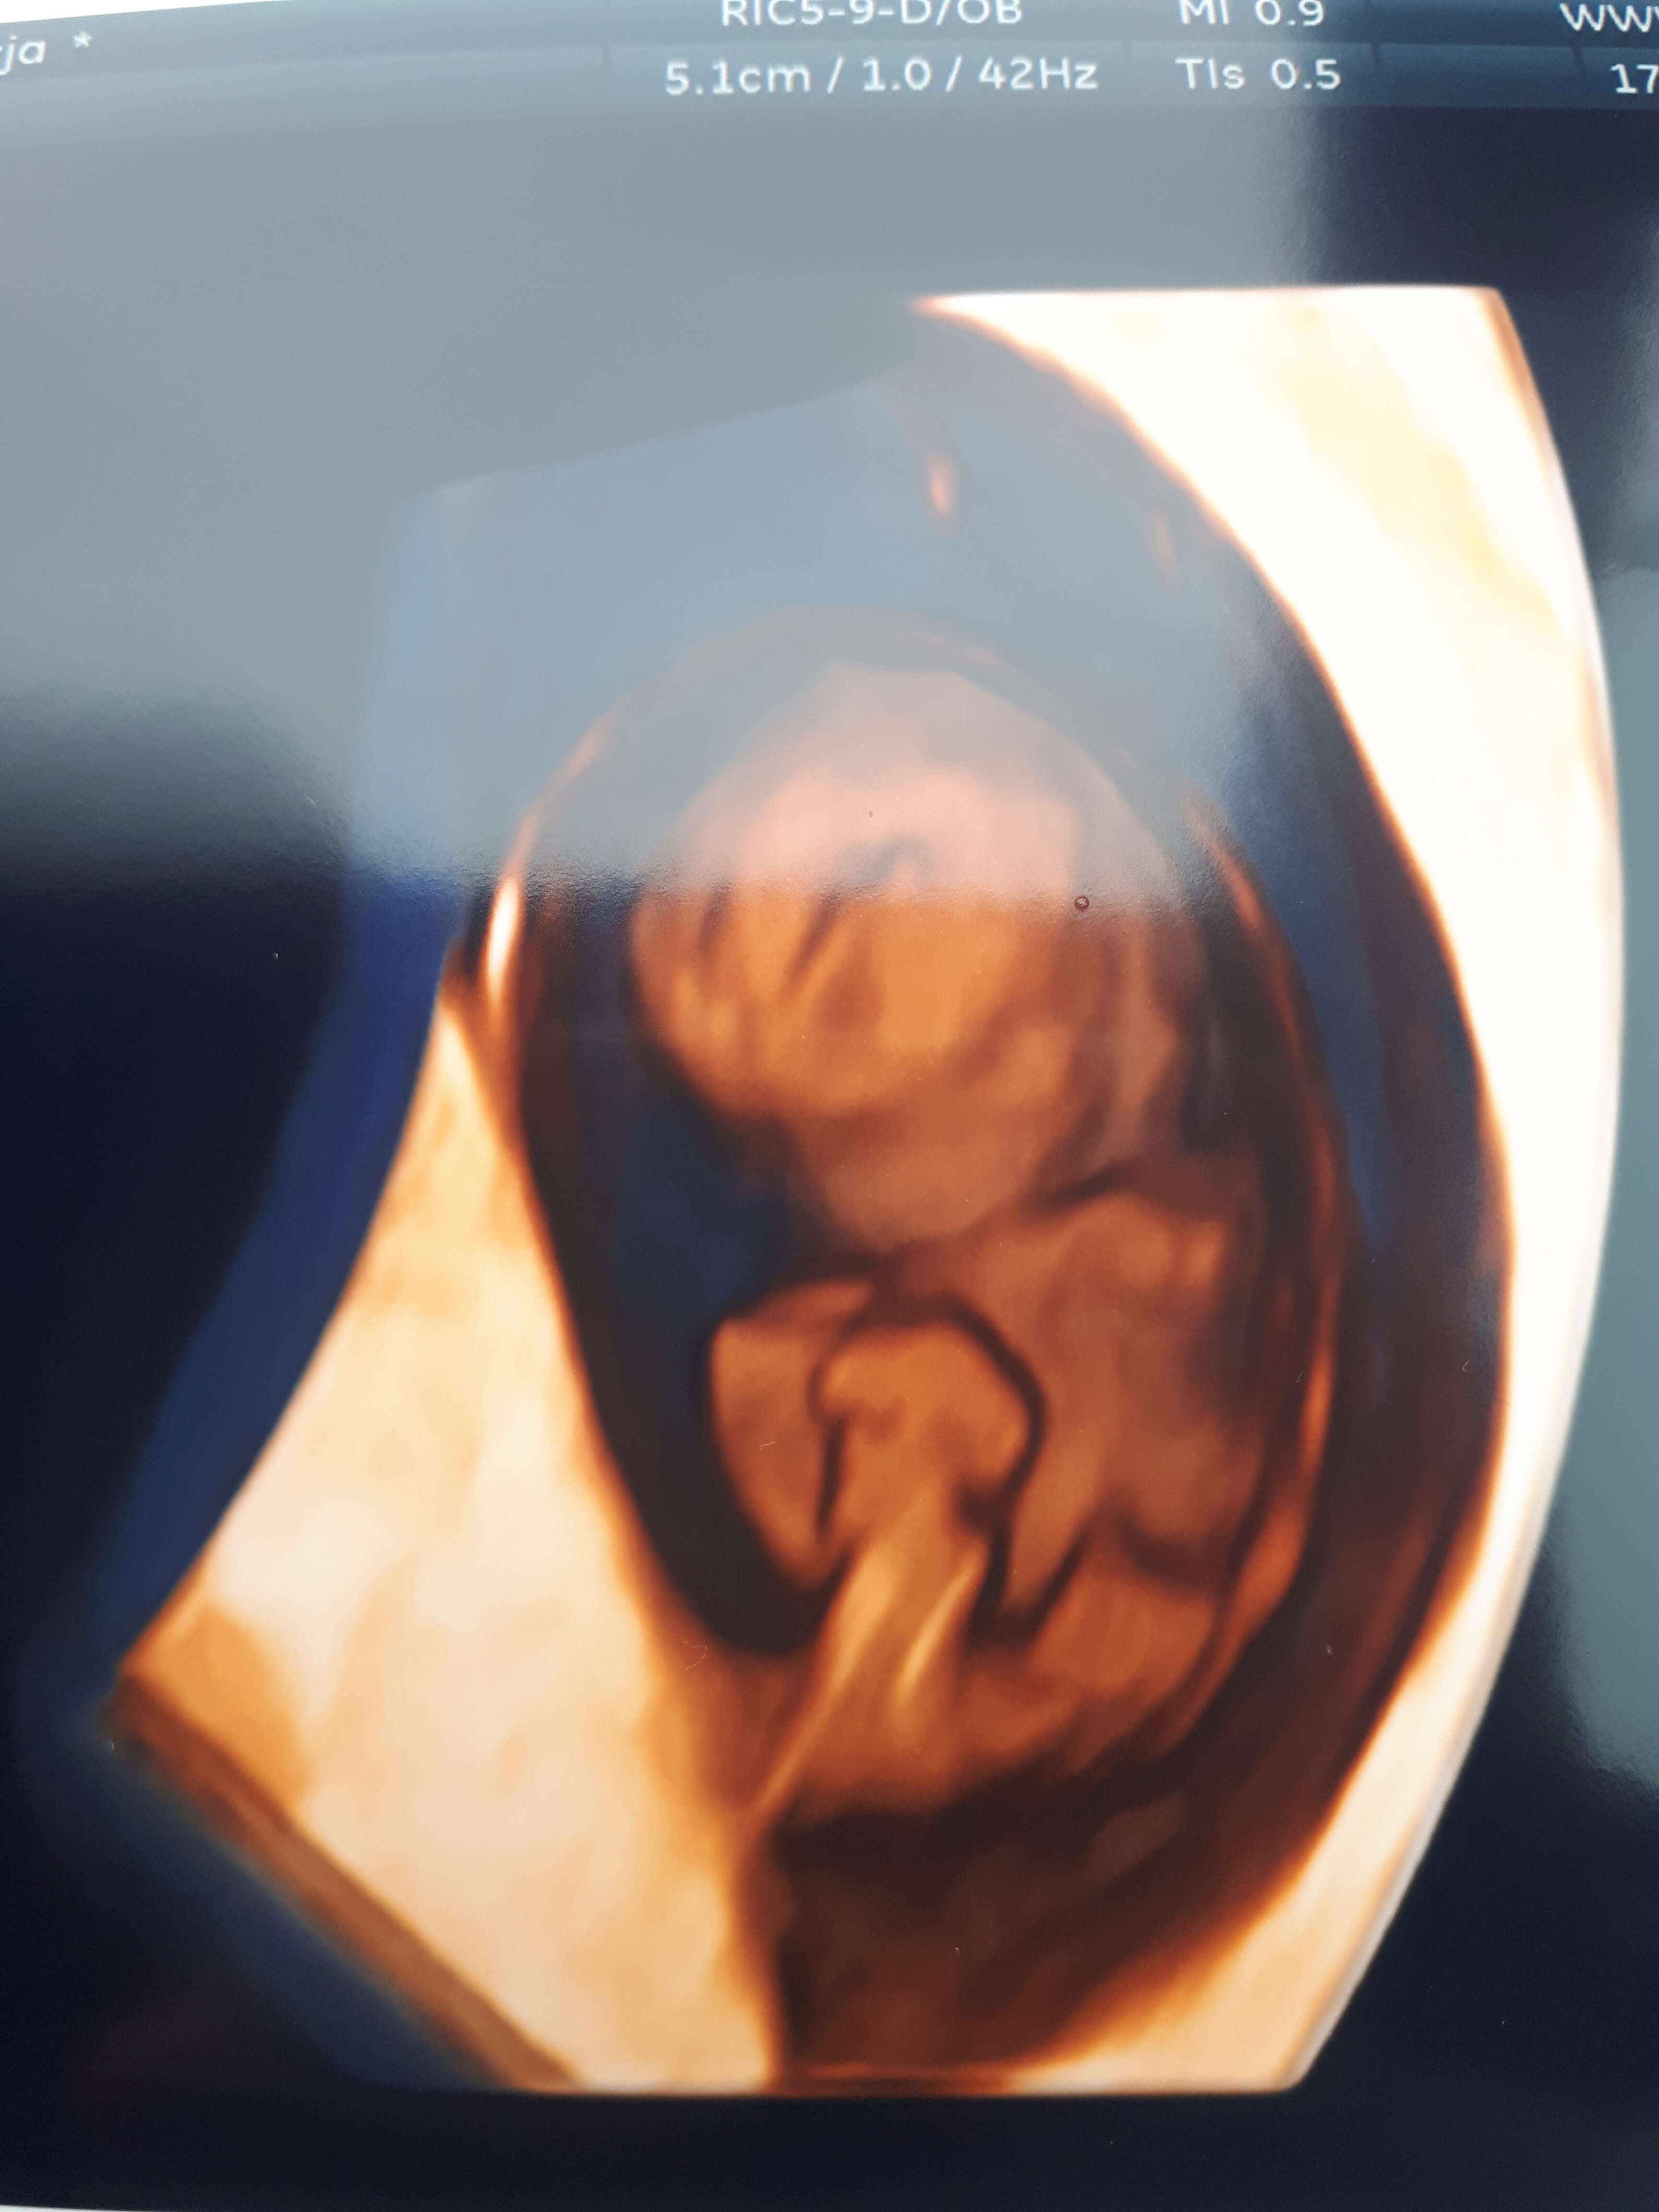

W ubiegły poniedziałek byłam na USG w innym miejscu (bo nie było terminu) i zarodek był malutki, wyszło spore opóźnienie co mnie zestresowało, ale nic nie pisałam, żeby się nie denerwować dodatkowo

A dziś okazało się, że super, już się zgadza z owulacją, wychodzi 9t4d

Zobacz załącznik 1317804